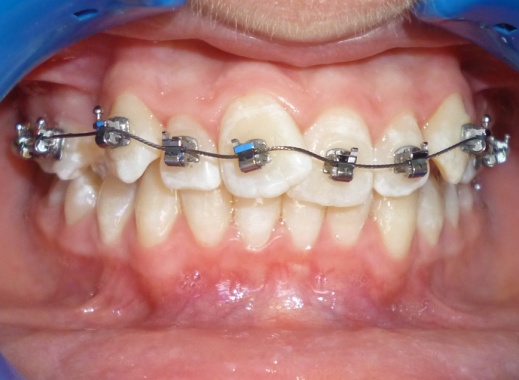

2 - Alignement par brackets autoligaturants

Le recul progressif des dents encombrées dans les espaces d’extraction créés à cet effet a été rendu possible grâce à l’utilisation de brackets autoligaturants, particulièrement efficaces pour respecter l’angulation et le torque des dents. Tous les espaces d’extraction ont été exploités pour résoudre l’encombrement, évitant ainsi tout recul des dents antérieures. L’occlusion obtenue est physiologique, en classe I canine et en classe II molaire thérapeutique.